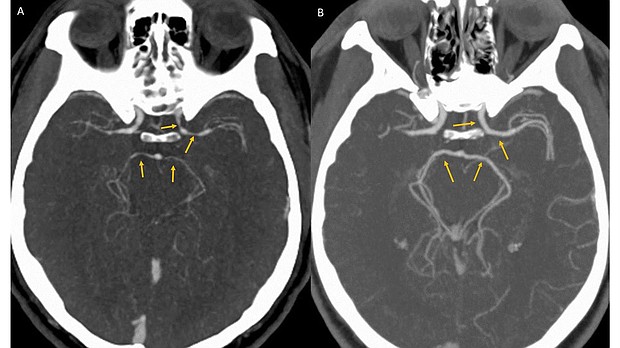

What happened to a contestant in a hot-pepper-eating contest may give spicy food aficionados one more reason to "fear the reaper," according to a recent case report.